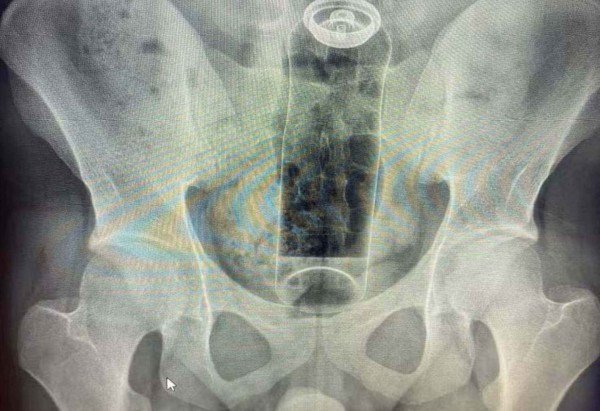

Um caso relatado nas redes sociais pelo cirurgião coloproctologista Daniel Brosco reacendeu o debate sobre como experienciar o prazer anal de forma saudável. No vídeo, o médico conta ter atendido um paciente de 19 anos que foi internado ao introduzir um desodorante no ânus durante uma brincadeira sexual. Como resultado, o produto subiu para o reto e o homem não conseguiu o retirar em casa.

Mesmo que seja uma zona erógena, a região anal pode “sugar” objetos devido aos movimentos peristálticos (contrações involuntárias responsáveis pelo funcionamento do órgão). “O canal anal tem um esfíncter forte, que fecha automaticamente, e o reto é uma cavidade que pode acomodar o objeto, principalmente se ele não tem uma base que fique do lado de fora”, explica Munhóz. “Em alguns casos, o objeto pode migrar para cima por movimentos naturais do intestino e pela formação de um tipo de vácuo, o que dificulta ainda mais a retirada”.

Entre os riscos associados à introdução de objetos não adequados no reto, destacam-se machucados na mucosa, cortes e sangramentos, fissuras, formação de hematomas e, em situações mais graves, perfuração do intestino e inflamação dentro do abdômen. “Além disso, quando o objeto fica preso, a tentativa de retirada pode piorar o trauma e aumentar o risco de infecção”, acrescenta o coloproctologista. “As complicações mais temidas são perfuração e infecção extensa, que podem exigir cirurgia e internação.”

O médico esclarece que o atendimento hospitalar deve ser procurado imediatamente no caso de um objeto introduzido não conseguir ser retirado manualmente. A emergência grave é caracterizada quando há sinais de perfuração, sangramento, infecção, dor abdominal forte e febre. “Nesses casos, o risco não é só local, pode evoluir para inflamação no abdômen e infecção generalizada”, justifica. “Mesmo sem esses sinais, se o objeto ficou preso e não sai facilmente, o mais seguro é ir ao pronto atendimento, porque a avaliação e a retirada precisam ser feitas com cuidado e com os recursos adequados.”